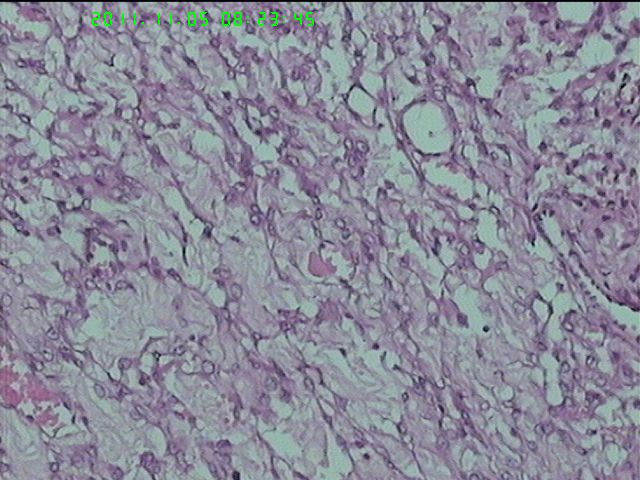

37岁女性患者,左卵巢肿块术中快速:恶性。术后左卵巢囊实性肿块14*9*5CM,灰黄色,部分乳头状,粘液样外观;子宫内膜厚1.5CM;网膜见多个小结节。图1--14左卵巢  15-19网膜  20--23宫腔

粘液腺癌(部分呈低分化)

在图中有明确浸润吗?好像看不出来,但是网膜显示非侵袭性。宫腔图片没有显示浸润。请多上边缘处图像。

请临床查有无阑尾病变,排除阑尾肿瘤转移后,如果没有明确浸润,倾向粘液性*交界性肿瘤伴腹膜种植,肠型。

总之先排除阑尾来源,再看有无浸润,有浸润才打癌。

卵巢粘液性囊腺癌伴内膜及网膜转移。

图1、4、5、6、11中可见疏松组织,网状结构,并见可疑透明小体,加上患者年纪较年轻,卵黄囊瘤不能除外,粘液腺结构可能是卵黄囊中的内胚层成分。且形态上与网膜结节相似。

左卵巢黏液性腺癌伴内膜网膜转移.